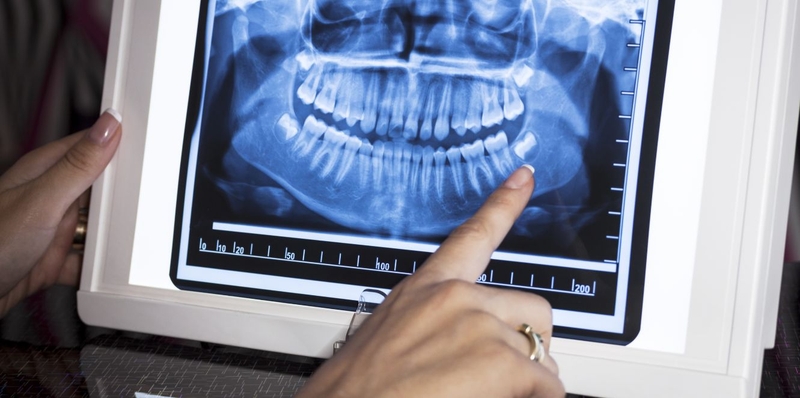

Chụp panorama răng 2

Bác sĩ có thể sử dụng hình ảnh X-quang để đánh giá tình trạng răng khôn